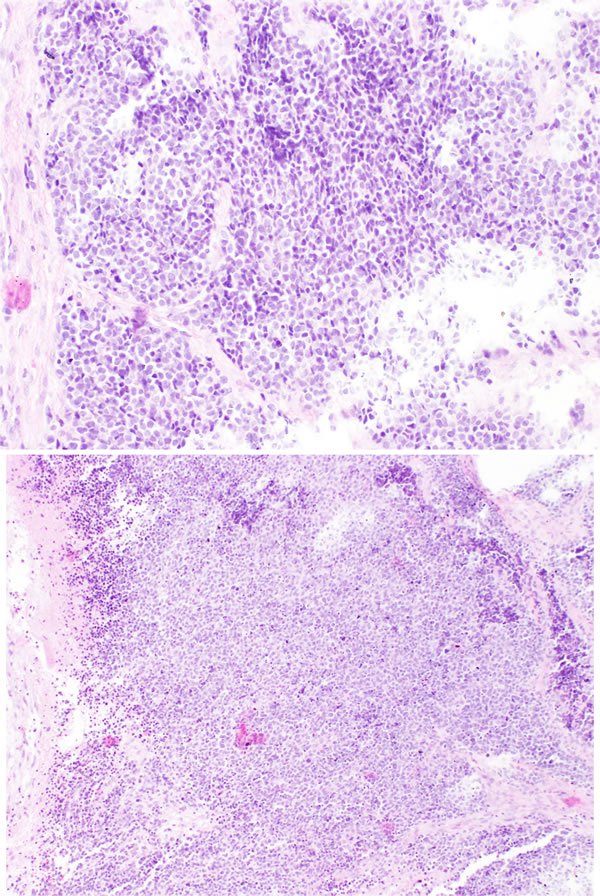

Grade I tumors have a lobular architecture with the presence of a prominent neurofibrillary matrix. The cells are small and cytologically uniform without mitotic activity. Pseudorosettes (Homer-Wright rosettes) are often present and necrosis is not seen. Grade II tumors usually show less prominent matrix and more cellular atypia with mitoses. Grade III tumors may retain a lobular architecture but the cells are more atypical with increased mitoses and necrosis. True neural rosettes (Flexner-Wintersteiner) may be present. Grade IV tumors are the most undifferentiated and difficult to diagnose because there is often loss of lobular architecture. Cytologic atypia, necrosis, and mitotic activity are often present. Figure 1 and Figure 2 show, respectively, the histology of low and high grade ONB. However, in our opinion Hyams’ grading system may have some limitations. First, it was originally created based on an observation of small group of patients (only 17 from Armed Forced Institute of Pathology) [43]. Additionally, some patient’s material used for confirmation of usefulness of this grade are taken from era before the identification of SNUC in 1990 and they might not have been reevaluated properly. It was shown that in non-specialized pathology department there is a huge overdiagnosis of small round cell tumors of sinonasal area as ONB. In only 2 of 12 tumors originally described as ONB the diagnosis confirmed in experienced Head and Neck Pathology Department [44].

Figure 1: Low grade ONB. Nests of small, monomorphic neoplastic cells with minimal cytological atypia.

Figure 2: High grade ONB. Neoplastic cells showing more diffuse pattern of growth. There is abvious cytological atypia of neoplastic cells.